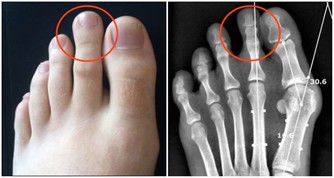

我的喉嚨偶爾會跑出米粒大小,黃白色的不明顆粒,

不會痛也不會不舒服,

但就是很臭,

這個症狀少說也有十幾年了,

我原本以為那是沒消化完的飯粒之類的,

後來我把關鍵字丟到谷歌,

才發現原來這是扁桃腺結石,

他耐心的用畫圖方式告訴我結石藏在扁桃腺的隱窩,不易清除,

另 外,蔡立泰醫師也表示,扁桃腺結石通常看起來像白色或微黃色的小石頭,有時候吐出來時,可以把這些小石頭壓碎,並出現臭臭的味道。扁桃腺結石目前 大多認為是由食物的殘渣及壞菌卡在扁桃腺表面的隱窩中所形成。有些人會感覺到喉嚨卡卡的感覺,嚴重的患者更可能出現頭痛、咽喉疼痛、吞嚥困難、耳朵痛癢、 甚至嘔吐等情形。也因為這些細菌和食物的殘渣以及部分壞死組織的鈣化,所以可能在講話時散發出一些腐爛的臭味,也就是我們所謂的口臭。